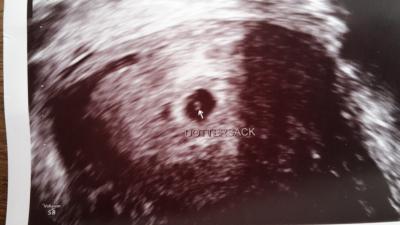

Hallo ihr lieben!!! Ich War ja heute beim Frauenarzt und wir konnten auch schon was sehen In zwei Wochen habe ich erneut einen Termin und bekomme dann den mutterpass. Ultraschall wird auch noch mal gemacht um zu schauen ob man das Krümel sehen kann:) Ich bin heute 5+1 Lg

Bild zu zurück vom Fa - Forum für Januar - Mamis